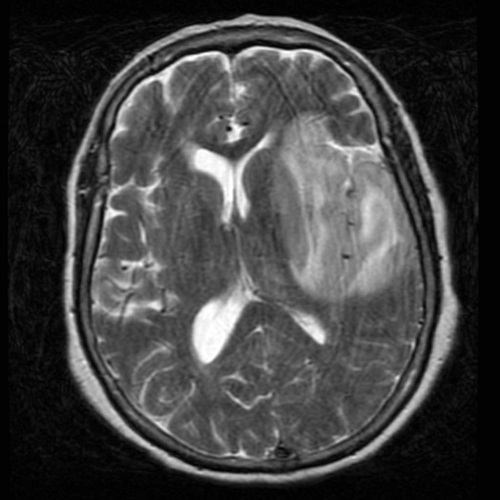

How does HSV Encephalitis it look on MRI

There is hyperintensity of the affected white matter and cortex in the medial temporal lobes and insular cortex.